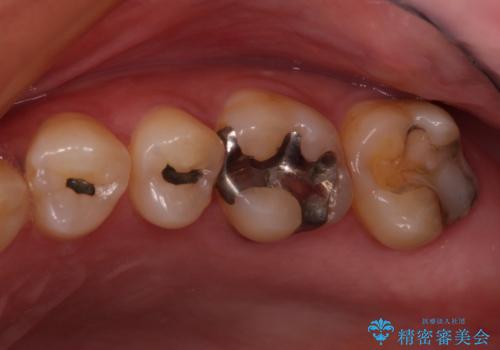

- 奥歯の銀歯がすぐに外れてしまうとのことで来院された患者様です。

何度か銀歯の詰め物を作ったものの、しばらくすると外れてしまうそうで、来院時には銀歯のない状態でした。

咬み合わせをみると、奥歯に負担がかかりやすいことが分かったので、適合がよく、硬さが歯と近いPGAインレー(白金加金合金インレー)にて修復治療を行うこととしました。